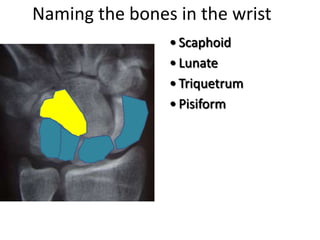

This document provides an overview of hand anatomy including:

- Naming the bones, joints, tendons, nerves and skin landmarks of the hand and wrist.